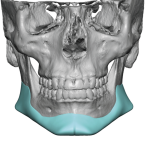

“Aesthetic temporal reduction” (often called temporal narrowing surgery) is a niche craniofacial procedure aimed at reducing the width of the head in the temple region (the area above and slightly behind the eyes). What it targets The temporal region (sides of the skull) Specifically: Temporal bone (outer skull) Temporalis muscle (a chewing muscle that can add bulk) How it’s done Read More…